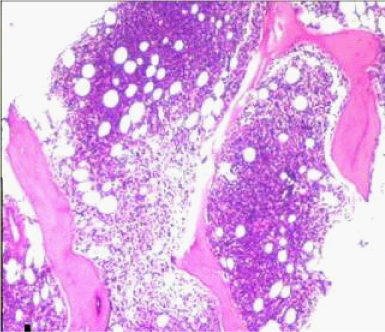

Bone marrow aspiration smears showed haemodilution, however imprint smears showed marked prominence of lymphoid cells constituting 70% of all nucleated cells. Bone marrow biopsy showed almost complete replacement by abnormal lymphoid cells arranged in vague nodular pattern, interstitial and intrasinusoidal pattern. It comprised of mainly small lymphoid cells having condensed chromatin and scant cytoplasm. The other population was of intermediate sized cells showing nuclear indentation and scant cytoplasm (possibly centrocyte-like cells). A significant number of intermediate sized cells showed moderate amount of pale eosinophilic cytoplasm (monocytoid cells). Interspersed in between were scattered large cells with evident nucleoli and cells showing plasmacytic differentiation [Table/Fig-3,4].

Photomicrograph of bone marrow biopsy showing nodular and interstitial pattern of infiltration (H&E 10X).